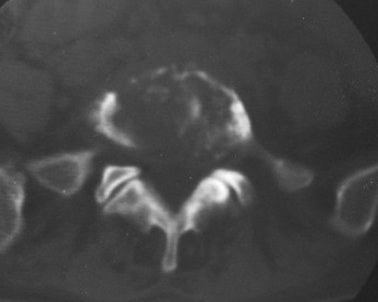

以下是引用织梦在2007-3-1 21:17:00的发言:[br]腰5椎体骨质碎裂,密度增高,边缘较毛糙,椎体内可见一斜行透亮线及骨质硬化,周围软组织肿胀不明显。本人认为还应该再仔细询问病史,看是否有外伤史。这个病例我考虑腰5椎体陈旧性骨折继发感染可能。

以下是引用dyqct在2007-3-1 18:04:00的发言:[br]腰5、骶1呈溶冰状骨质破坏,边界清楚,无明显硬化,内见多数沙粒状死骨,周围软组织肿胀。[br]考虑:腰5、骶1结核,建议严格抗结核治疗后复查。

以下是引用gaoxiao在2007-3-1 18:02:00的发言:[br]腰5骶1椎体见骨质破坏,其内见死骨形成,椎前软组织肿胀,感染性病变,腰骶椎tb。